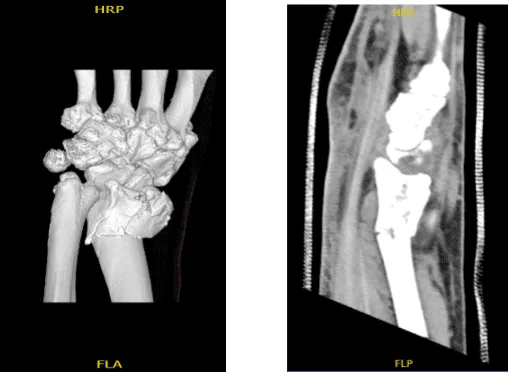

El médico revisó y discutió una resonancia magnética; Existe una fractura distal conminuta del radio con extensión intraarticular donde el desplazamiento puede alcanzar hasta 3 mm. También está presente angulación cubital. Existen cambios degenerativos en el triscafo y en las primeras articulaciones carpometacarpianas.

La fractura se conminió en más de tres partes con extensión intraarticular. La fractura se redujo manualmente y luego se fijó con múltiples hilos K y se revisó mediante fluoroscopia. Al encontrarla en una posición aceptable, se colocó una placa volar y se fijó con el uso de cables K con punta de bola.

La foto se volvió a tomar para confirmar la buena reducción. La placa se fijó a la fractura mediante tornillos de bloqueo y de no bloqueo. Un Tornillo se desperdició. también extraer el fragmento distal con la placa. Se tomaron fotos entre medias y luego se hizo y guardó la foto final. Se consideró que estaban en una posición aceptable.

Tras dos semanas, el paciente fue atendido en la consulta para sus visitas postoperatorias, con radiografías de la muñeca izquierda. Mostró que la placa quirúrgica y los tornillos atraviesan una fractura oblicua incompletamente cicatrizada del radio distal izquierdo. El hardware parece intacto.

Existen cambios degenerativos leves en la primera articulación carpometacarpica. No hay subluxaciones ni luxaciones, no hay cuerpos extraños radiopacos y se observa una leve hinchazón de tejidos blandos. Aparte de eso, el paciente niega tener fiebre, escalofríos y dolor bien controlados.